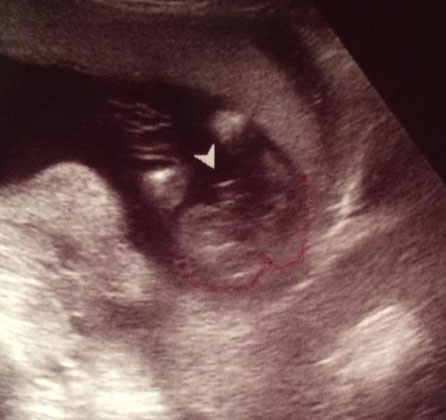

Ladies, went in for our 16 week ultrasound and came out this photo. Just wanted to get other moms opinions. it looks nothing like my sons did (second photo) and his was done at 16 weeks as well. up close it looks like an owl haha